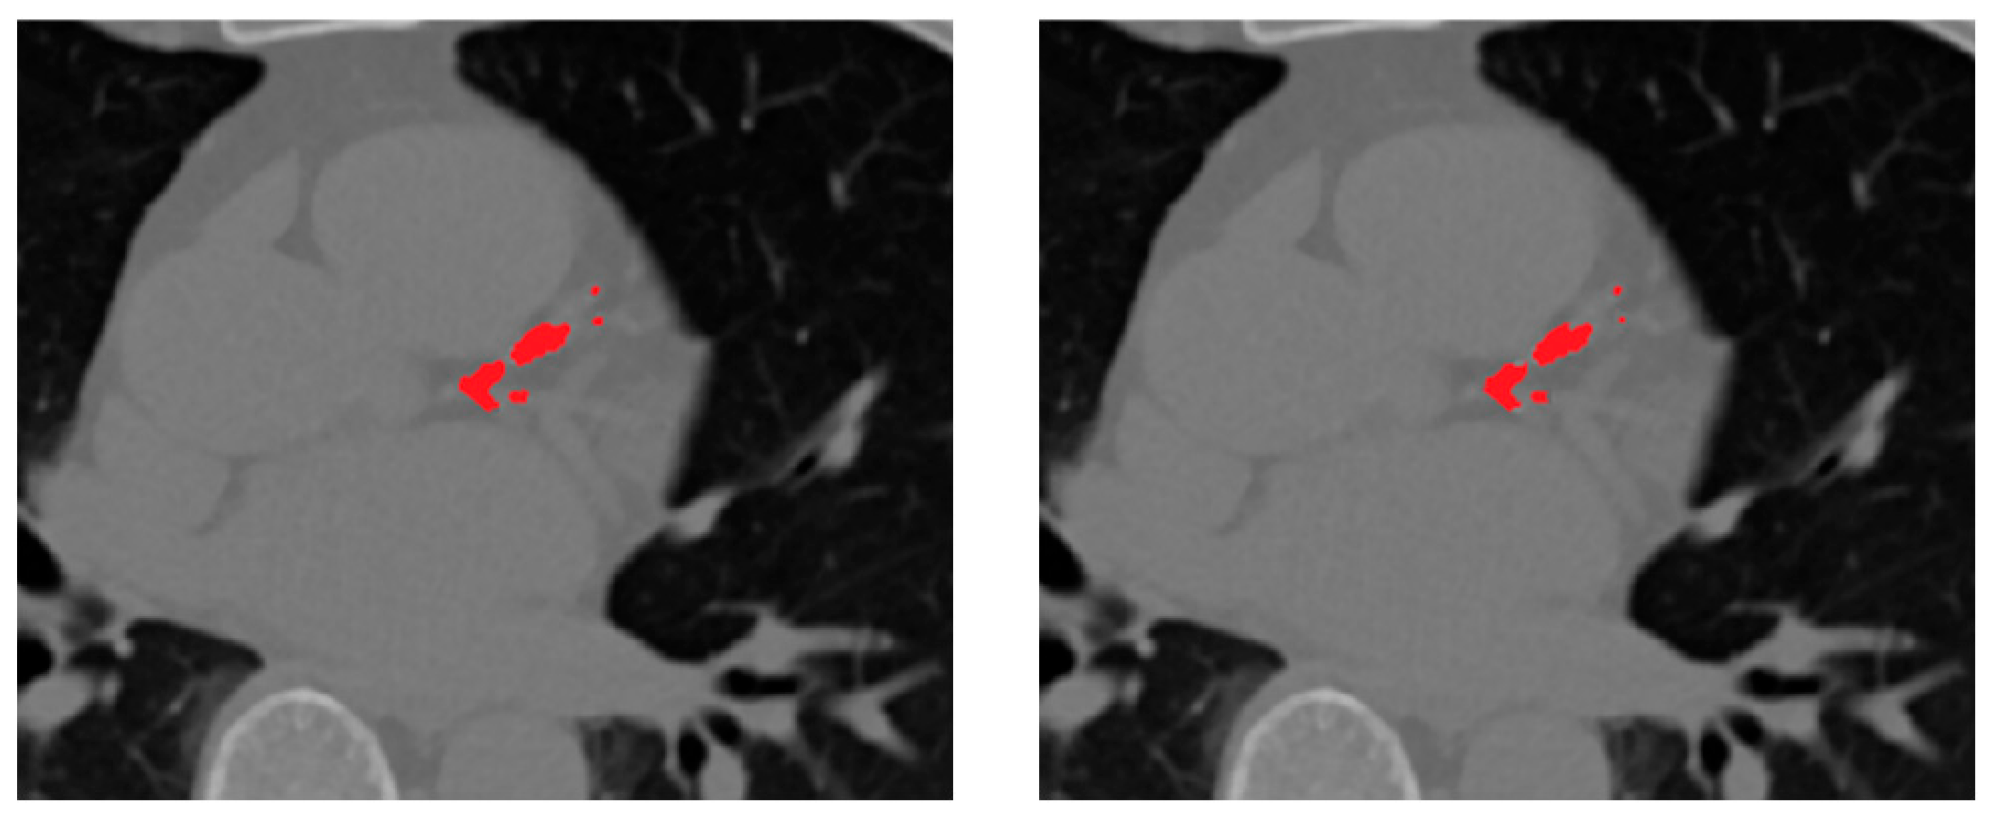

Figure 6. Qualitative comparison of segmentation results for coronary artery calcification (CAC). (a) ground truth mask, (b) proposed selective ensemble, (c) Residual U-Net, (d) UNet++, (e) Attention U-Net, and (f) baseline U-Net.

Figure 6 presents qualitative comparisons between the segmentation outputs of the proposed ensemble and the individual U-Net variants. From left to right, each panel shows the ground truth mask, followed by predictions from the selective ensemble, Residual U-Net, UNet++, Attention U-Net, and baseline U-Net. The visual results highlight the superior boundary delineation and reduced false positives achieved by the selective ensemble. In particular, the ensemble produces more coherent and anatomically accurate segmentation of small calcified lesions along coronary branches, while the baseline models tend to over-segment adjacent high-intensity structures such as aortic walls or valves. The qualitative evidence thus reinforces the quantitative findings, confirming that rank-based fusion not only improves numerical accuracy but also enhances clinical plausibility and visual consistency in CAC segmentation.